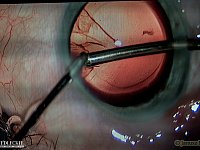

Pokonać zaćmę